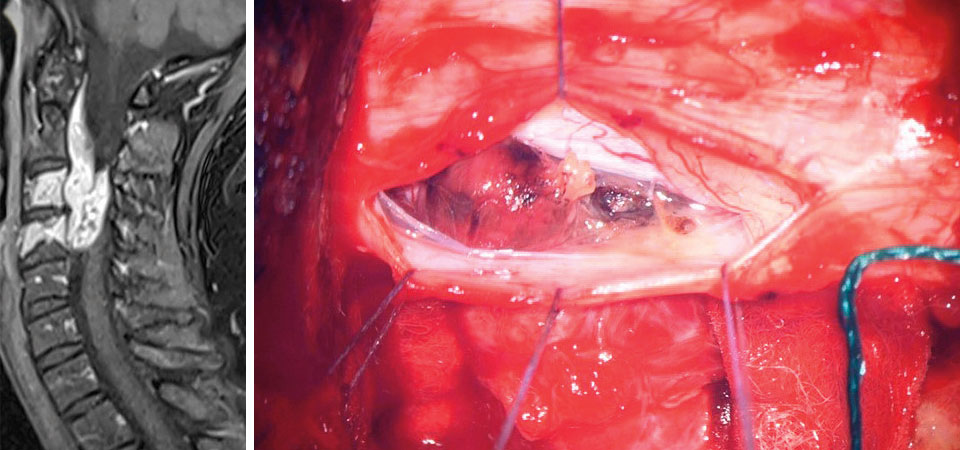

Fall 4

Ein 82-Jähriger kam mit Sensibilitätsstörungen an beiden Händen, Gangunsicherheit und einer ungerichteten Fallneigung bei geschlossenen Augen in die Klinik. Die Magnetresonanztomographie zeigte eine intramedulläre Raumforderung auf Höhe HWK 3/4. Die Histologie nach Resektion brachte ein melanotisches Schwannom ans Licht. Dieser extrem seltene Subtyp birgt ein 10%iges Malignisierungs- und Metastasierungspotenzial und bedarf deshalb nach der Entfernung einer MRT-Kontrolle. Spätestens beim Rezidiv ist eine Radiatio angezeigt.